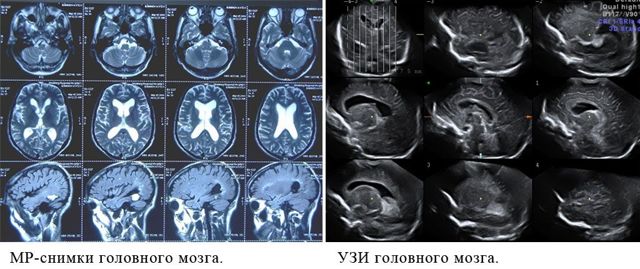

МРТ сосудов мозга и головы — это комплексное обследование как вещества и оболочек головного мозга, так и его сосудистого русла. Такое комплексное исследование можно сделать в любом МРТ центре СПб и включает оно два сканирования, которые проходят друг за другом: МРТ головного мозга; МРТ сосудов головного мозга (она же МРТ ангиография сосудов головного мозга).

Сравнение диагностической ценности

Как УЗИ головного мозга, так и МРТ используются для оценки состояния сосудов, снабжающих мозг. Исследуются структура сонных артерий и внутренний слой кровеносных сосудов, чтобы вовремя обнаружить обызвествление и атеросклеротические бляшки и начать лечение. Для обследования самого мозга применяются нейросонография (у грудных детей) и транскраниальная сонография.